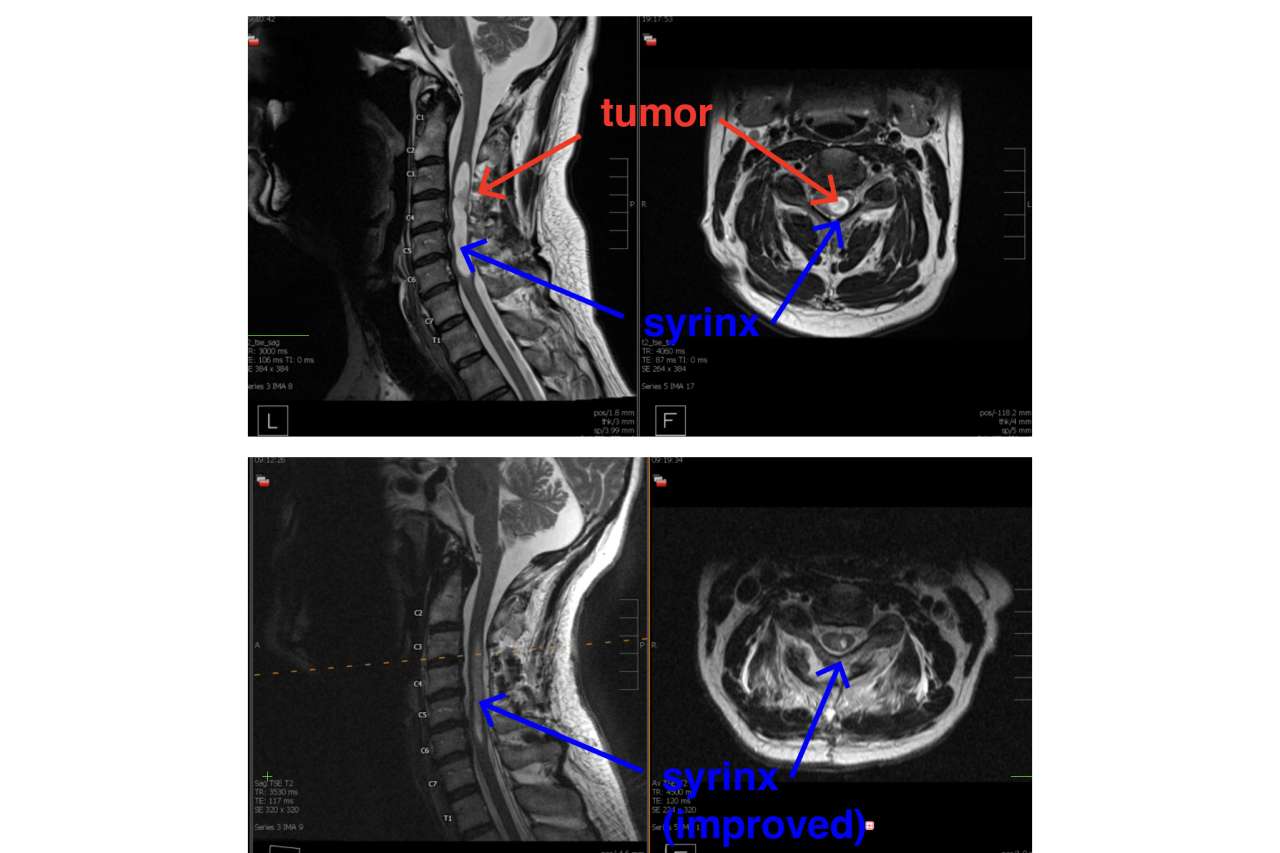

Before and after MRI of spinal tumor removal

MRIs of the spine before and after the tumor removal. (UCLA Health Neurosurgery)

After ordering additional MRIs of Daniels’ entire spine, Dr. Vivas diagnosed him with a rare spinal tumor. The hemangioblastoma, having formed spontaneously, was slowly growing in the blood vessels of the neck’s cervical spine. It was likely benign, and unlike a malignant tumor, wouldn’t move or grow to other areas.

However, the tumor was blocking the flow of spinal fluid, which accumulated and caused a syrinx.

“The spinal cord swells up as if there's a water balloon inside,” said Dr. Vivas, also an assistant professor of neurosurgery, orthopedic surgery and radiation oncology at the David Geffen School of Medicine at UCLA.

Sitting right on the whitish-beige surface of the spinal cord was the tumor, orange-colored like a sunset, and about the size of a pea.